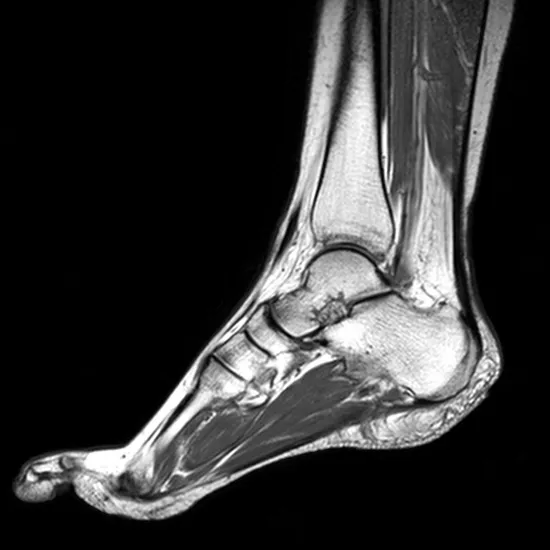

A foot MRI can provide comprehensive images of bones, cartilage, tendons, muscles, blood vessels, and ligaments, allowing your doctor to determine the source of discomfort and any further damage it has caused.

A doctor may request an MRI scan of a foot or feet to diagnose pain or discomfort. An MRI can detect bone or joint problems.